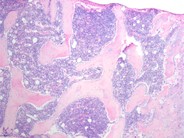

The patient is a 10 month old Caucasian male with a history of recurrent upper respiratory infections and otitis media since birth. His CBC at this time included a H/H of 10.9g/dl/32.4%, platelet count of 280,000/ul and a WBC of 3840/ul with a differential of 25% monocytes, 70% lymphocytes, 4% eosinphils, 1% basophils and 1% neutrophils. His ANC was 38/ul. After an extensive evaluation he was diagnosed as having congenital neutropenia consistent with Kostmann's syndrome. The peripheral smear confirmed the leukopenia and almost complete absence of neuutrophils. A single hyposegmented PMN can be seen in this view.